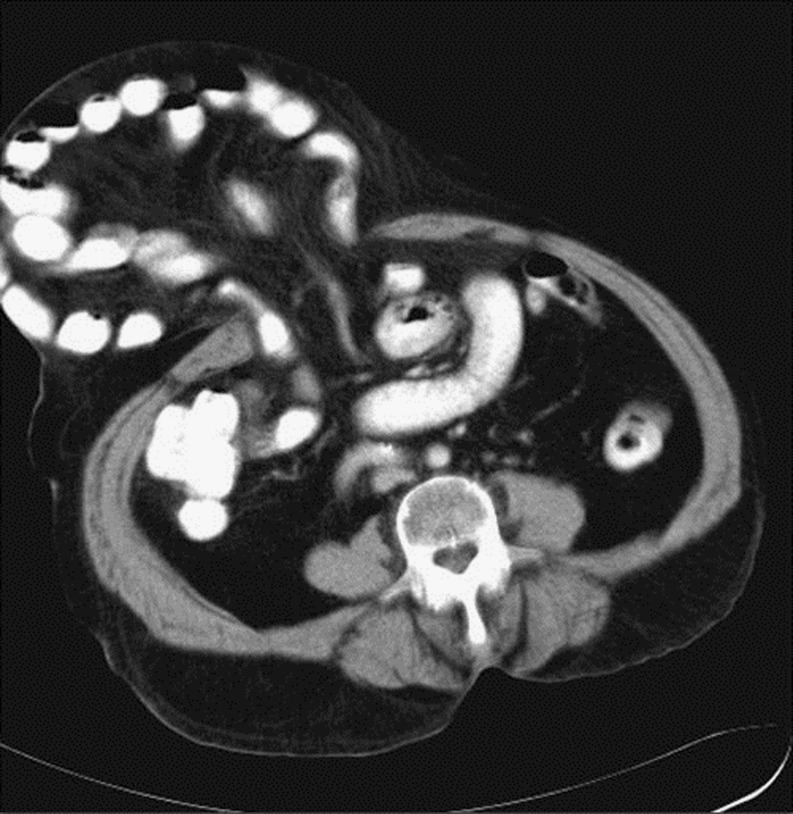

Traumatic Diaphragmatic Hernia

Diaphragmatic rupture can result following major blunt trauma to the lower thorax or abdomen in up to 6% of patients [29, 30]. It is more common on the left side due to an area of congenital posterolateral weakness on the left side and protective effect of the liver on the right hemidiaphragm [31–34]. Helical CT with thinner axial images and higher quality of reformatted images has proven to be more valuable in preoperative detection of traumatic diaphragmatic hernia (Fig. 11).

Fig. 11.

Traumatic diaphragmatic Hernia (a–b) CT scan shows discontinuity in right posterolateral part of diaphragm along with free fluid and herniation of colon into the right chest

CT signs of diaphragmatic injury include direct visualization of injury (free edge of the disrupted diaphragm demarcating the defect is seen), segmental diaphragm non-visualization (low specificity), intrathoracic herniation of viscera, collar sign (focal constriction of the herniated bowel or omentum ) which shows a high specificity of 80.7–100% [31, 32], dependent viscera sign (viscera lies dependent against the posterior chest wall) which shows a specificity of 71–96.5% [32], diaphragm thickening, intramuscular hematoma and peridiaphragmatic active contrast extravasation.

The most commonly herniated viscera is the stomach and colon on the left side and the liver on the right side.